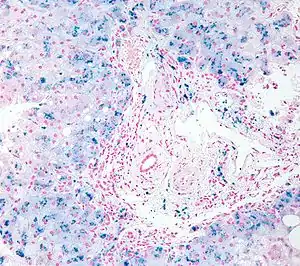

| Micrograph of a liver biopsy showing iron deposits due to iron overload. Iron stain. | |